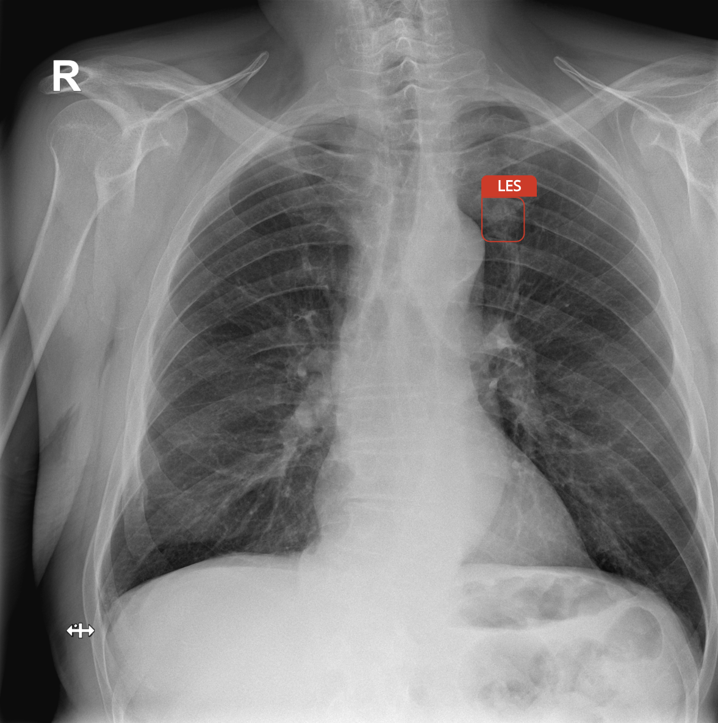

Ano. Lidské oko má své limity, zatímco AI dokáže odhalit i malé léze, které mohou být ukryté mezi žebry nebo u klíční kosti. Dobré natrénování AI modelu a správně nastavené algoritmy umí rozpoznat jemné změny ve struktuře plicní tkáně, které mohou znamenat rizikovou abnormalitu. AI někdy dokáže odhalit i drobné textury, které jsou běžným okem těžko rozpoznatelné. A přitom tyto změny mohou souviset s nádorovou lézí či jinou plicní poruchou.

Abych to ilustroval, Carebot nedávno označil „podezřelou lézi“, která měla tvar žraloka. Ukázalo se, že pacient měl na košili připnutý odznak s touto parybou. AI samozřejmě netušila, že jde o dekoraci – vyhodnotila tvar podle toho, co znala. To je další příklad, proč jsou AI metody pouze doplňkem či pomocí při diagnostice nádorů a finální rozhodnutí musí být vždy na lékaři.